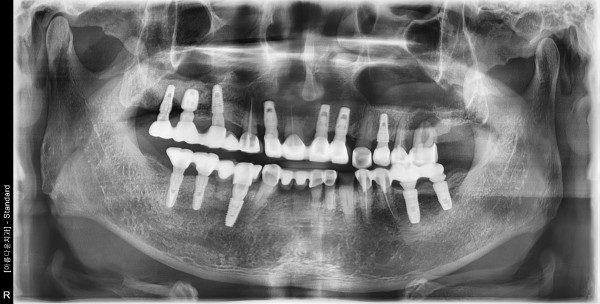

69세 남자환자 / 좌측상악 발치 및 뼈이식, 임플란트식립